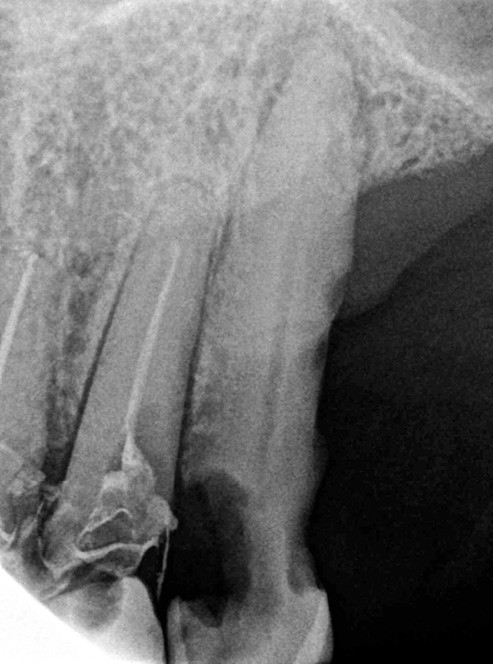

Un patient de 84 ans, en bon état de santé générale, consulte pour la perte de trois couronnes solidarisées métalliques 17, 16 et 15 qui permettaient la rétention d’une PAP à châssis métallique (fig. 1 à 5).

– 17, 16 sont à l’état de racines, 15 est déjà préparée et ne présente aucune symptomatologie pulpaire ;

– 12 est couronnée et présente une mobilité importante et un épaississement ligamentaire ;

– carie radiculaire importante à la 21 ;

– 22 est couronnée et présente également une carie radiculaire ;

– 13 est très cariée et présente une alvéolyse dépassant le tiers apical de la racine.